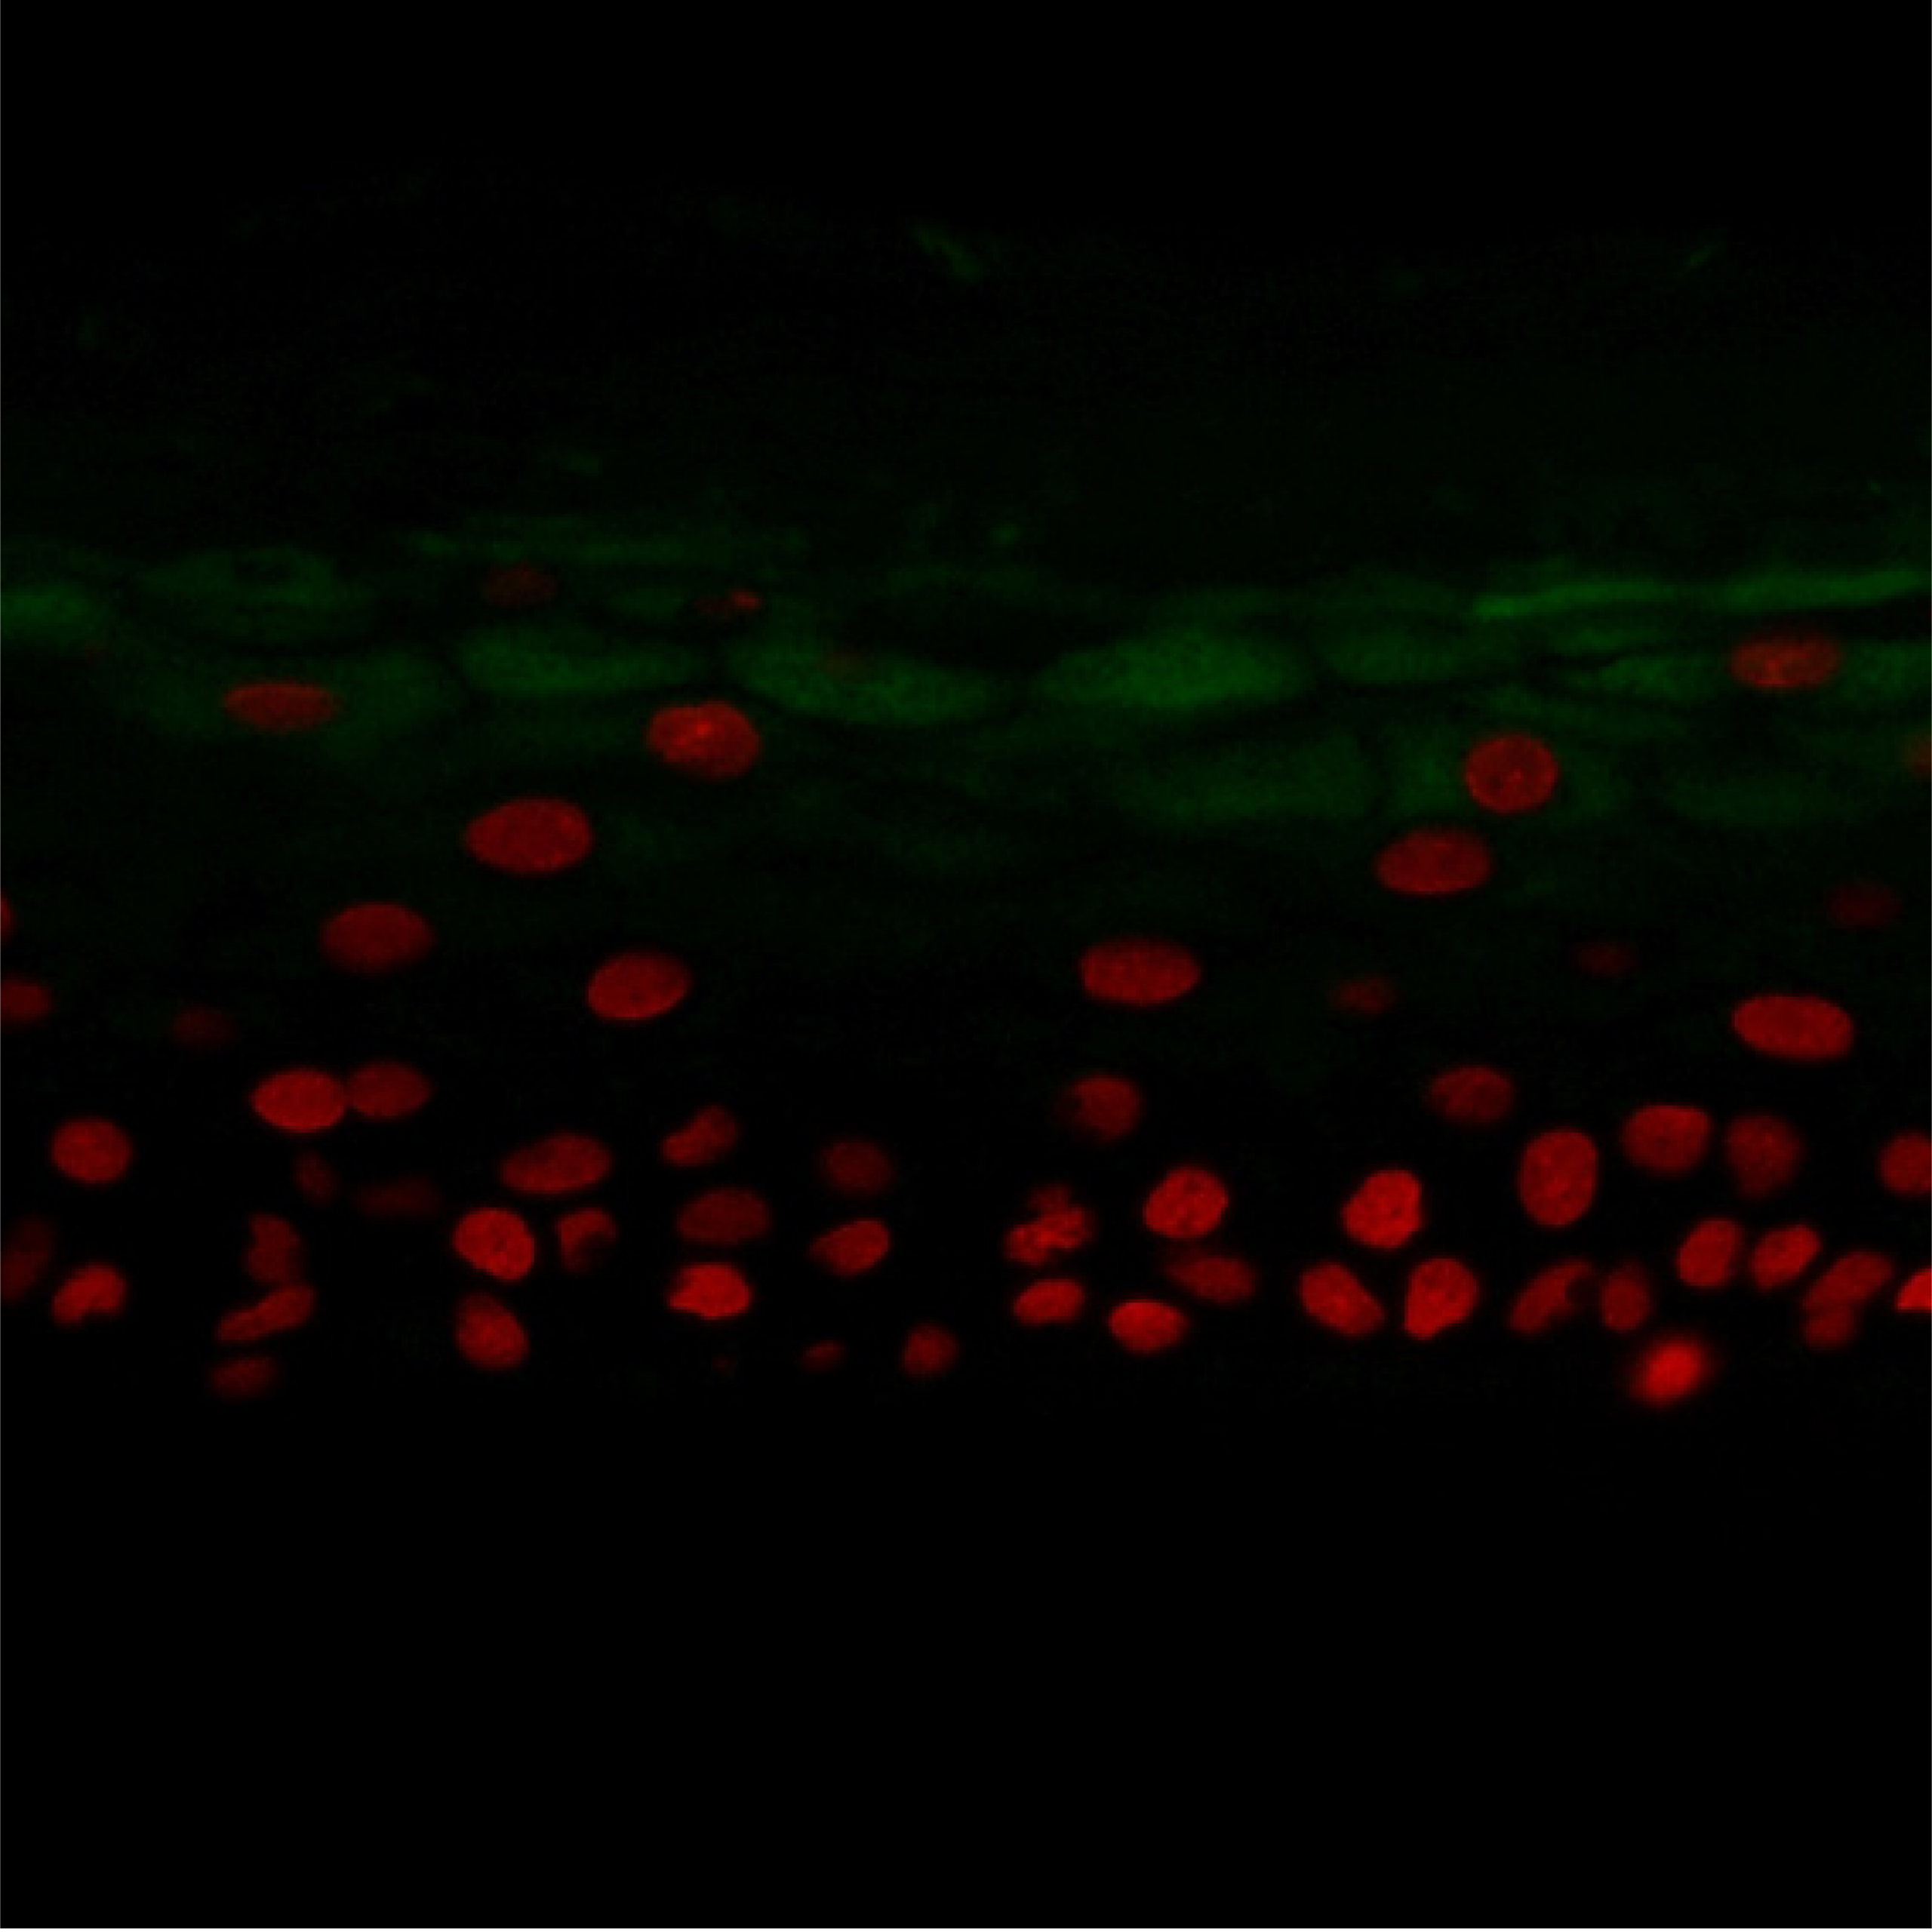

HYPERKÉRATINISATION

Test : Différenciation des kératinocytes

Intérêt : L’hyperkératinisation se caractérise par une desquamation anormale des kératinocytes, entraînant l’obstruction des follicules pileux.

Méthode : Immunohistochimie (coloration verte : filaggrine)

Modèle : Épiderme humain reconstruit (RHE)

Interprétation des résultats : La filaggrine est un composant clé du stratum corneum, et peut, à ce titre, être observée dans les couches externes de l’épiderme. L’ajout du composé test réduit le nombre de cellules de la couche cornée, comme l’indique la diminution de l’expression de la filaggrine dans l’épiderme.